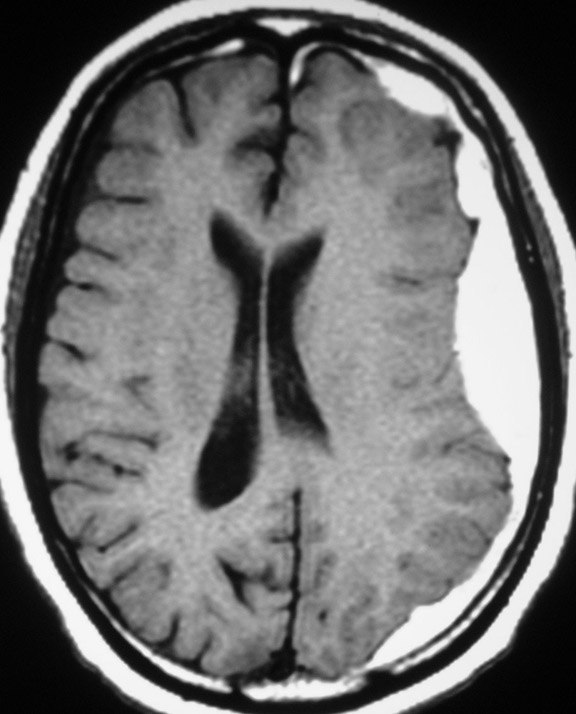

Отличие субдуральной и эпидуральной гематом головного мозга

Судбуральная гематома (в "форме банана")